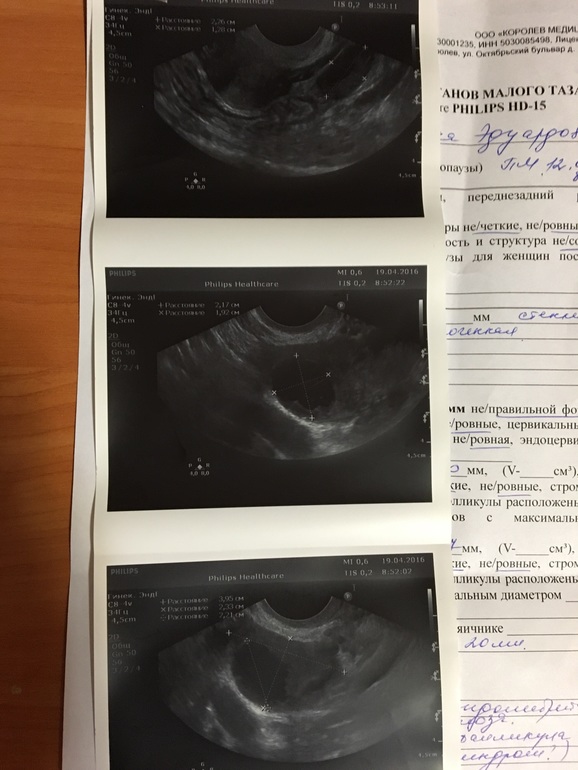

2 разных результата УЗИ

Короче я офигела за 2 дня у меня появилась миома, двурогая матка и эндометрий уменьшился на 2 мм!

Сказала, что мой врач ваще ничего не понимает и всё плохо, а у них типа крутой аппарат узи! Но на мой "непрофессиональный взгляд" первое узи 2 дня назад, как то правдоподобнее выглядит!

Прилагаю фото, какое на Ваш взгляд правдоподобнее?

второе фото не совсем информативно многое не написано, я бы больше поверила первомк фото.

Второе фото мой врач, вся инфа в карте, большая часть на словах объясняется, заключение так для архива, по второму я верю что была О, т. к. Чувствовала ее вчера, но не более, даже по изображению на мониторах небо и земля! И сегодняшняя сразу стала рекомендовать себя свою клинику, оки и гомеопатию, как то не вызывает доверия(

обычно на словах узи не объясняют это все таки бумага и маленький но документ.

по изображению даже гинекологи не смотрят в основном все руководствуются описанием на бумаге.